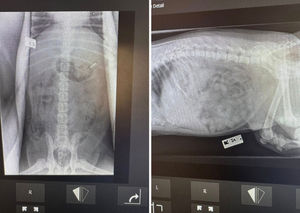

An X-ray later confirmed his owner's suspicions - and Charlie was taken in for emergency surgery on New Year's Eve.

"X-rays confirmed the owners suspicions, so Charlie had emergency surgery to remove it as it was the only option.